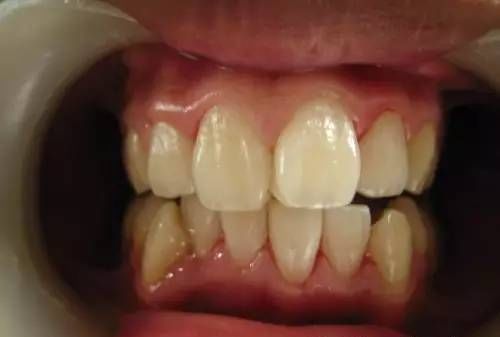

定期洗牙是目前最有效的治疗牙周疾病的方式。下面是洗牙前后的对比图:

洗牙(洁治)后,洁白如一

洗牙(洁治)后效果很明显